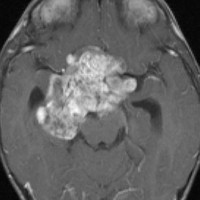

化学療法が有効なのは,上の画像のようにガドリニウム増強で強く増強されるタイプです,またT2強調画像で強い高信号になるものほど化学療法が有効です,要するに毛様粘液性星細胞腫の要素に化学療法が有効であるということです

この毛様細胞性星細胞腫はガドリニウムでほとんど増強されません(右側のMRI)から,化学療法を行っても小さくなりませんので,手術摘出する必要があります,実際に視床下部から発生したもの視交叉が犯されておらず,手術亜全摘出できました